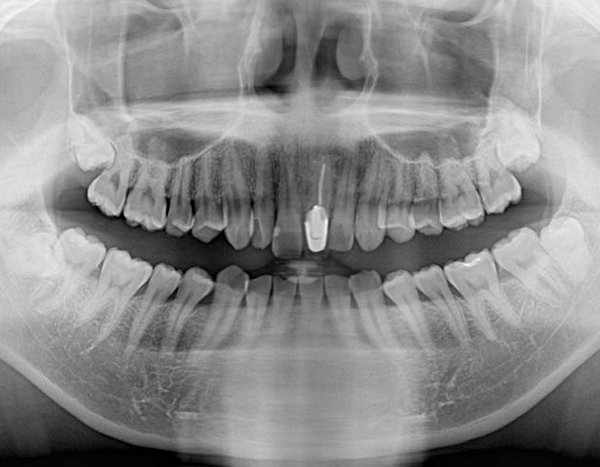

STEP 02検査&検診

短時間で安全に親知らずを抜歯するためには、事前の画像検査が欠かせません。CT撮影により、親知らずや顎の骨の状態を詳しく知ることができます。その上でお口の中を拝見します。現状と歯科医としての意見をお伝えし、患者様と話し合いながら、抜歯を行うのか、残して経過観察に留めるか決定します。

検査&検診